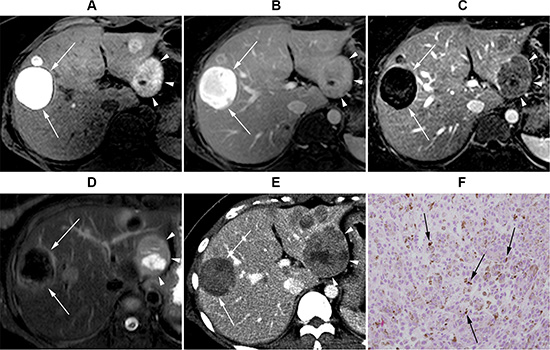

Figure 2: Gadoxeticacid-enhanced liver MRI of a 36-year-old female with uveal melanoma. (A) Precontrast T1-weighted image. (B) Post-contrast portal venous phase T1-weighted image. (C) Subtraction image (portal venous phase – precontrast T1 weighted image). (D) T2 weighted image. Segment 2 lesion (4.2 cm, arrowheads) displays positive enhancement on the subtraction image and intermediate high T2 signal intensity (SI), whereas segment 8 lesion (4.5 cm, arrows) displays negative enhancement and low T2 SI. (E) CT scan image at the same level obtained 2 months later. The segment 2 lesion (arrowheads) size has increased to 6.0 cm, whereas segment 8 lesion (arrows) is still 4.3 cm. (F) Histopathological examination [hematoxylin and eosin (H&E) stain ×200] of liver biopsy obtained from the segment 2 lesion revealed tumor cells with abundant intra-cytoplasmic melanin pigments (arrows), consistent with malignant melanoma.